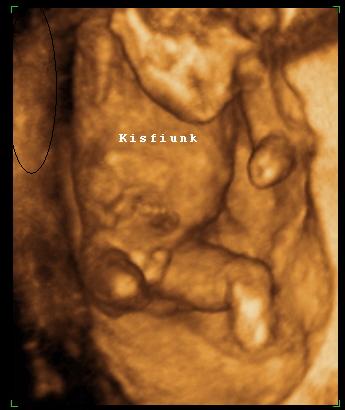

Nagyon boldog névnapot a pici fiúnak!